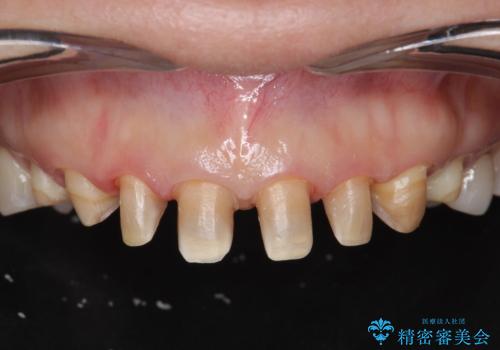

- 十数年前に行った、前歯のラミネートベニアの継ぎ目が見えるようになってきて見た目が気になる。

この際もう一度ラミネートでやり替えるのではなく、強度にも優れるクラウンにしたいと希望され来院されました。

ラミネートを丁寧に除去したのち、ジルコニアクラウンを作製し審美性の回復・向上を計画します。